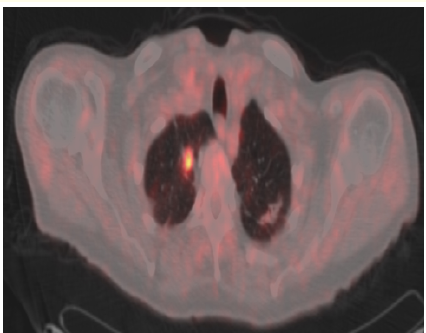

Solid Pseudopapillary Tumor of the Pancreas: A Case Report

Lamara Abdelhak, Medjahdi Sid Ahmed, Gadda Mounir, Boukhane Mohamed, Nahida Harchouche, Bloulou Mamed Lamine, Saadna Adlene and Selmani Khaled. 6(7): 12-18.